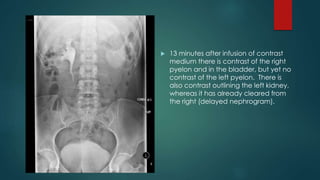

 13 minutes after infusion of contrast

medium there is contrast of the right

pyelon and in the bladder, but yet no

contrast of the left pyelon. There is

also contrast outlining the left kidney,

whereas it has already cleared from

the right (delayed nephrogram).

 Two hours after infusion you can appreciate a

distension of the left ureter and a

hydronephrosis of the left pyelon.

 This examination demonstrates the typical IVP

features of collecting system dilatation and a

delayed nephrogram secondary to a distal

obstructing calculus. In this case, the calculus is

well seen radiographically.